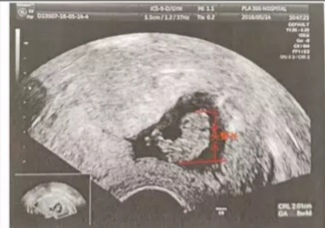

第三部曲心搏 心搏是宝宝的灵魂,一般在孕7-8周出现,只有心搏的出现才提示宝宝存活,最晚在CRL0.7cm时出现心搏。心搏的出现提示胎儿发生胎停的概率大大减少。